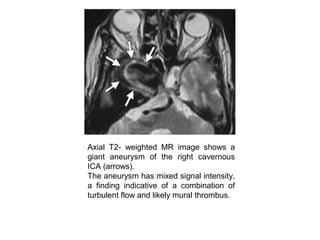

Axial T2- weighted MR image shows a

giant aneurysm of the right cavernous

ICA (arrows).

The aneurysm has mixed signal intensity,

a finding indicative of a combination of

turbulent flow and likely mural thrombus.